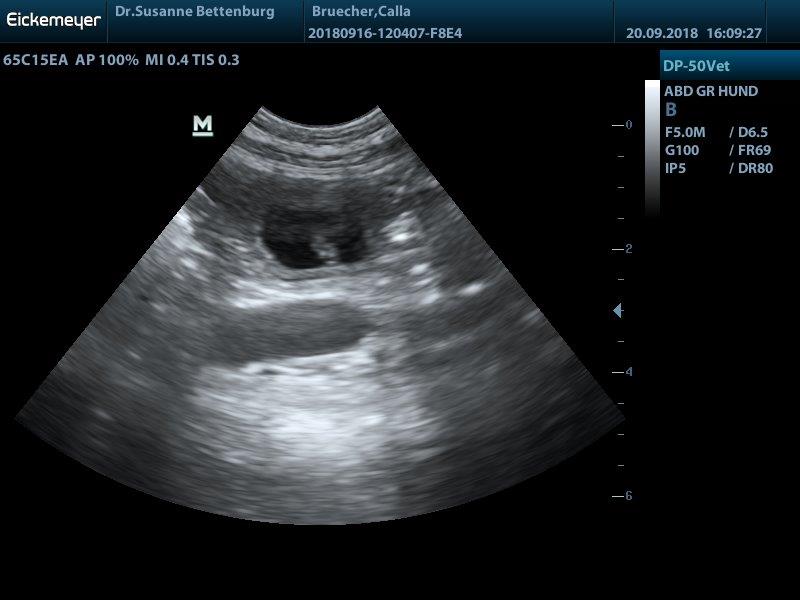

Juhuuu Calla ist trächtig...

wir haben viele kleine Baby's gesehen und erwarten ende Oktober einen normal großen Wurf